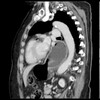

What pathology is shown here?

Esophageal Atresia